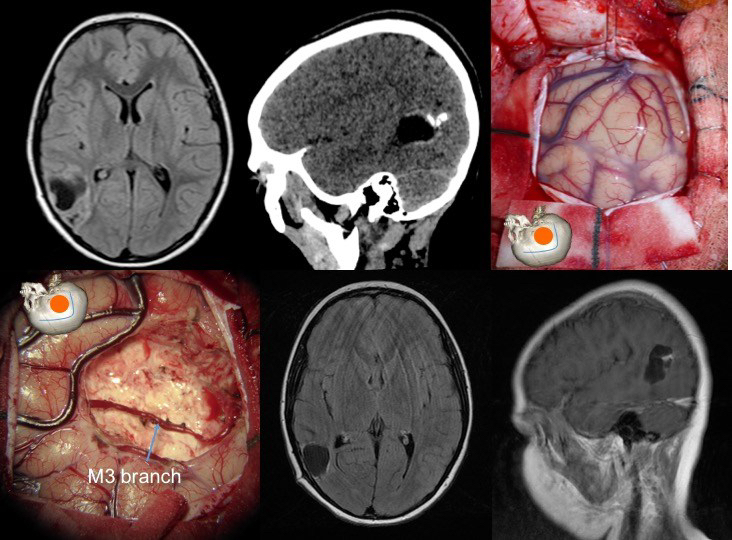

les tumeurs insulaires

elles peuvent être localisées à l’insula, ou l’envahir à partir de la région temporale ou frontale. en profondeur, elles sont en contact avec les noyaux gris centraux et la capsule interne.

- on les aborde en ouvrant la vallée sylvienne, en restant sur le versant temporal pour éviter de léser la région frontale postérieure

- les branches de la sylvienne sont séparées du cortex insulaire tumoral

- la dissection vasculaire peut entraîner un vasospasme, elle devra donc être particulièrement douce.

- il est préférable chaque fois que possible de réaliser une dissection sous-piale pour limiter la contamination de la vallée sylvienne, puis de suivre les limites tumorales.

- la partie postérieure du pédicule temporal contient les radiations optiques, et doit être respectée.

- la résection tumorale se fait par aspiration pour limiter le plus possible la dissection profonde d’avec la capsule interne et les noyaux gris.